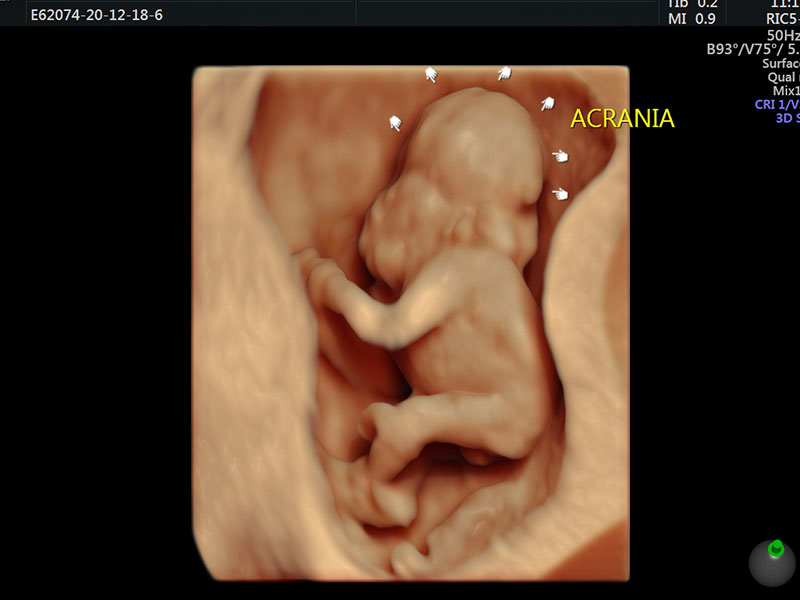

Sometimes improper growth could be a cause of concern and on the other side, there are certain disorders which are identified in this scan, some could be rare congenital heart anomalies related to fetalbrain,face, thorax,heart,GIT,renal, skeletal etc